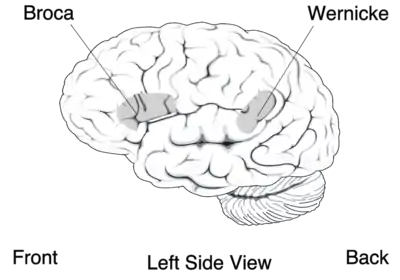

La principale est l'aire motrice primaire qui occupe toute la partie postérieure du lobe frontal, juste en avant du sillon central. Elle est organisée de façon somatotopique (chaque zone du corps recevant une afférence d'une partie précise de cette aire), la surface associée à un muscle étant proportionnelle à la précision des mouvements dont il est capable : le visage et la main sont donc fortement représentés. Comme pour la somesthésie, il existe ici un homoncule moteur. On y trouve l'aire de Broca (cf. image de droite) dont l'atteinte est responsable de l'aphasie de Broca[21], une maladie dans laquelle une personne peut exprimer sa pensée sous forme de phrases cohérentes, mais ne peut pas les prononcer. Le rôle de l'aire motrice primaire est d'effectuer les mouvements volontaires. Les afférences des neurones de cette zone sont croisées : l'hémisphère gauche commande les mouvements de la partie droite du corps et inversement.

- le lobe pariétal contient la zone d'association sensorielle qui intègre les données en provenance de tous les systèmes sensoriels pour donner une image de l'ensemble de l'environnement. Il comporte aussi une petite zone impliquée dans le langage, l'aire de Wernicke, dont la lésion entraîne l'aphasie de Wernicke qui se différencie de l'aphasie de Broca par le fait que le malade peut former des phrases grammaticalement et syntaxiquement justes, mais sans signification ;